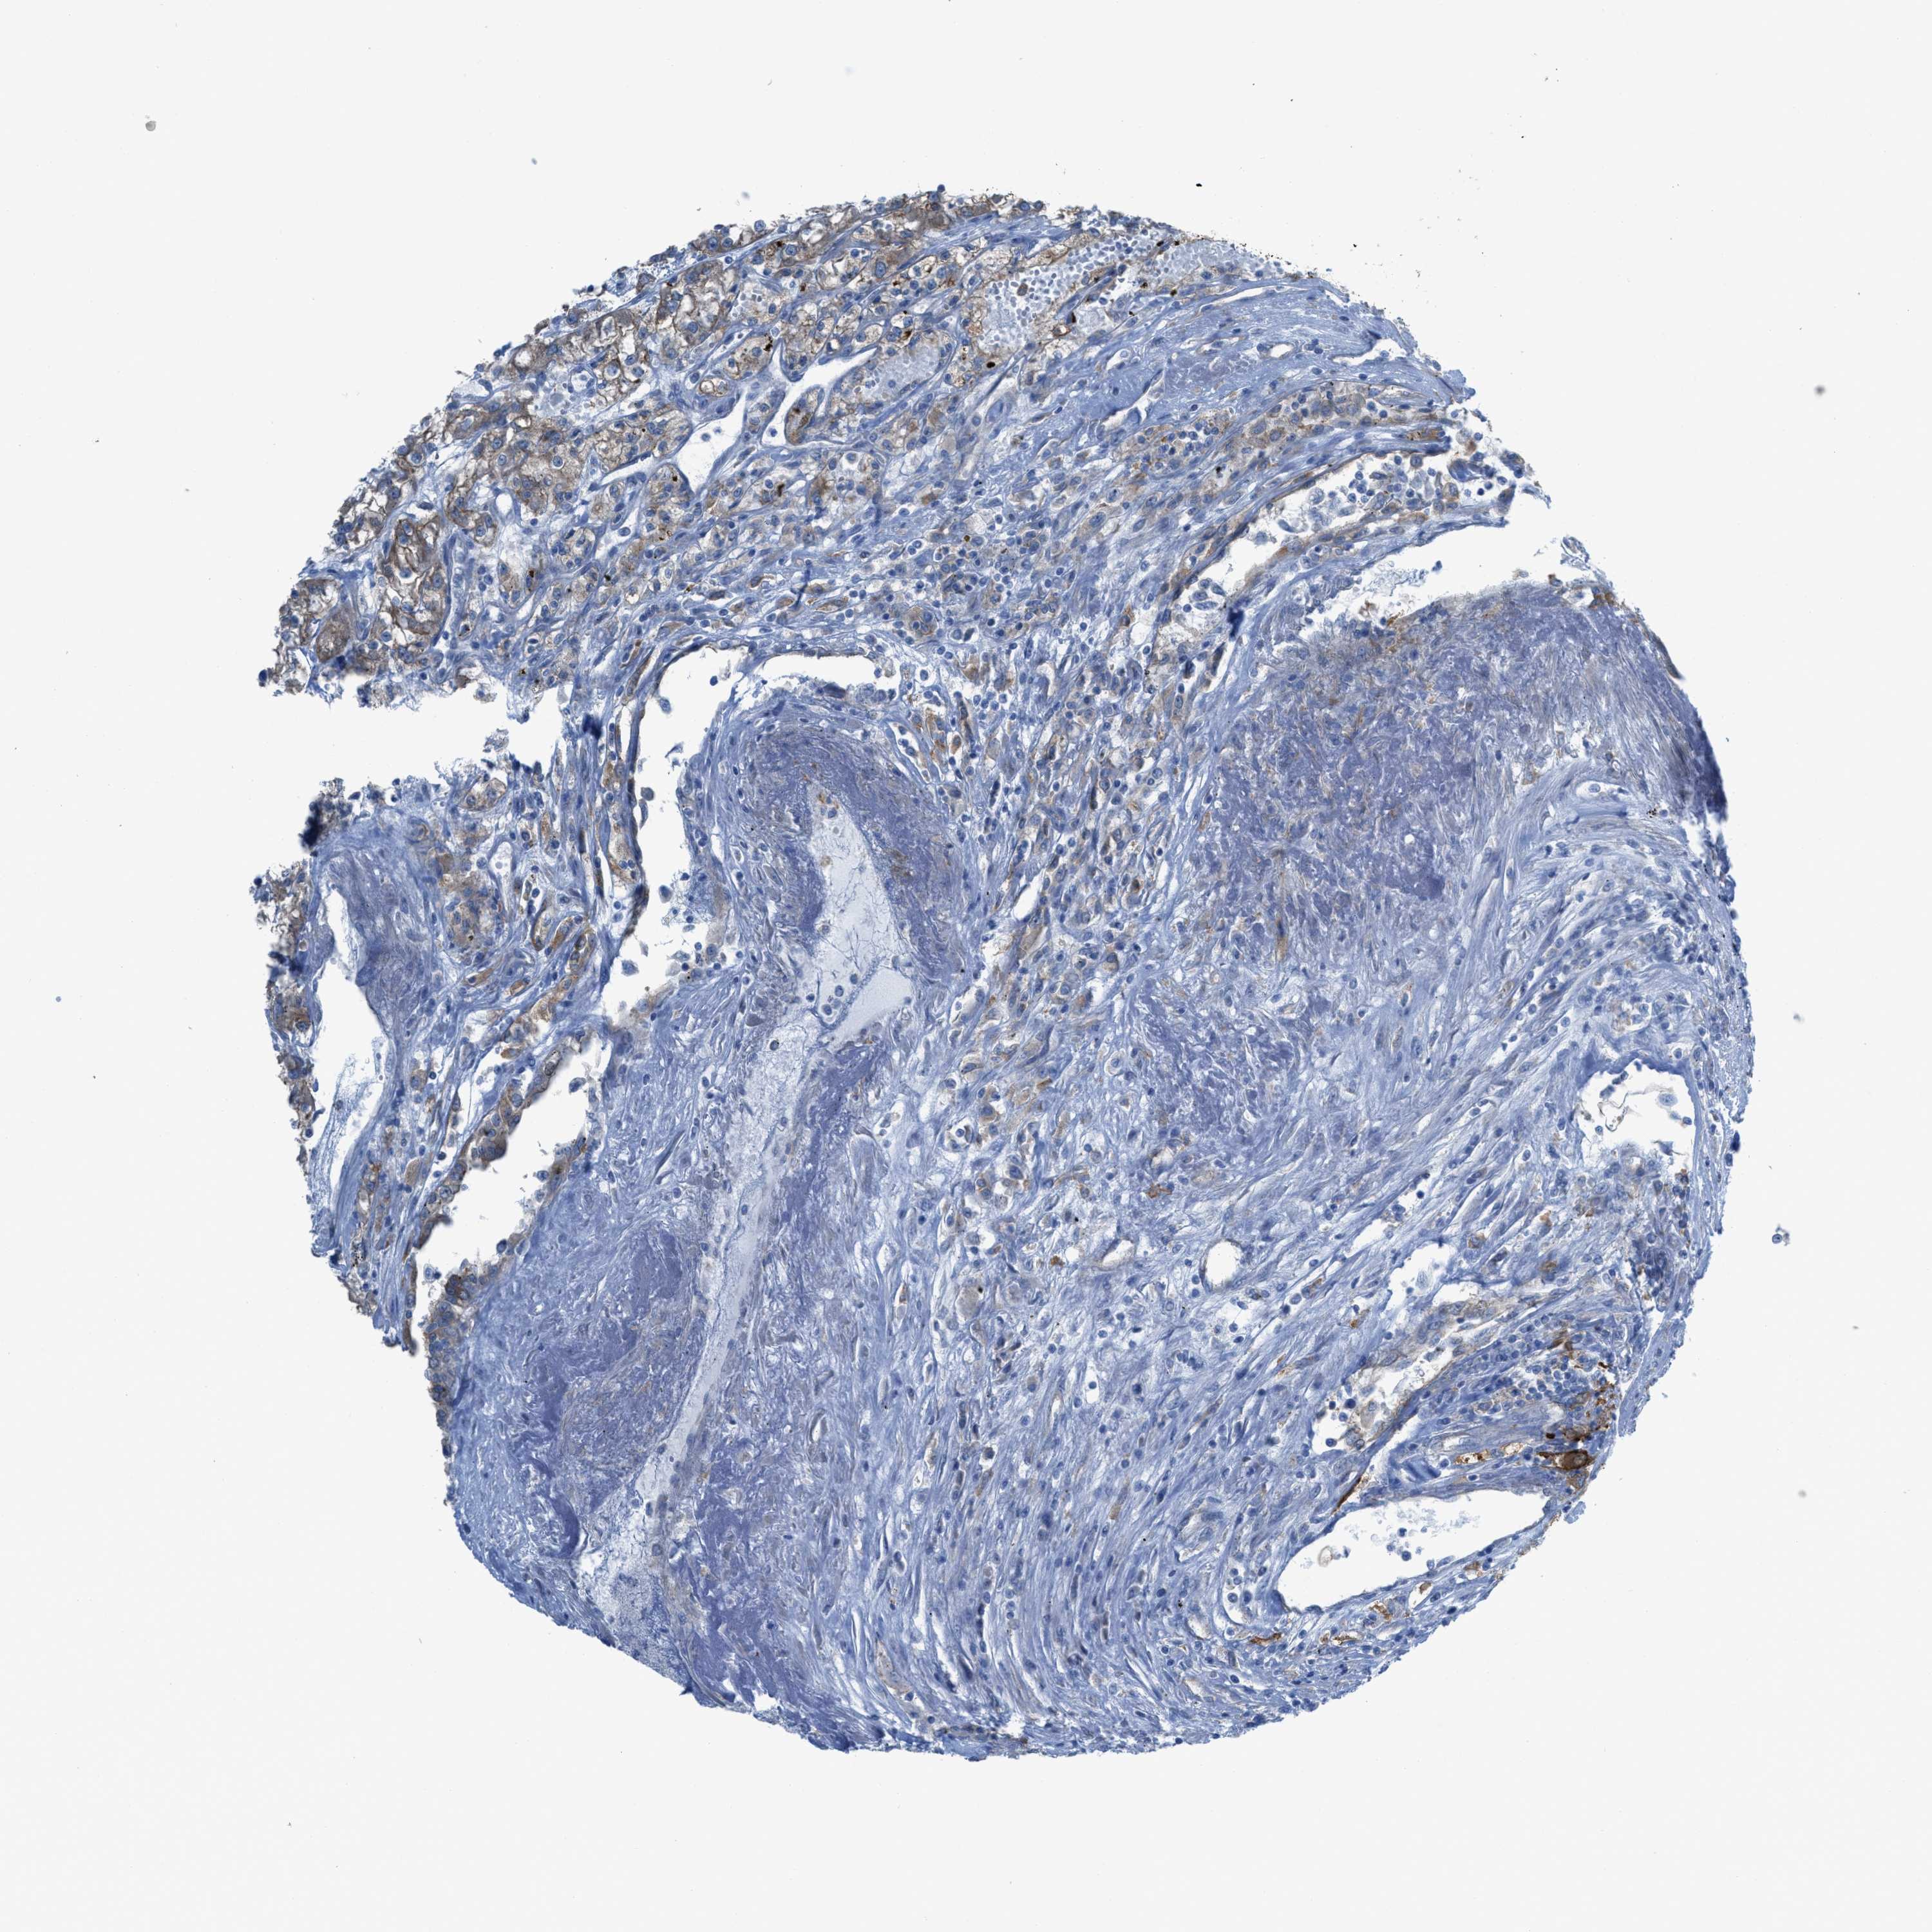

CANCER RENAL CANCER Show tissue menu

KICH TCGA KIRC TCGA KIRC VALIDATION KIRP TCGA PROTEIN RCC CPTAC PROTEIN EXPRESSION